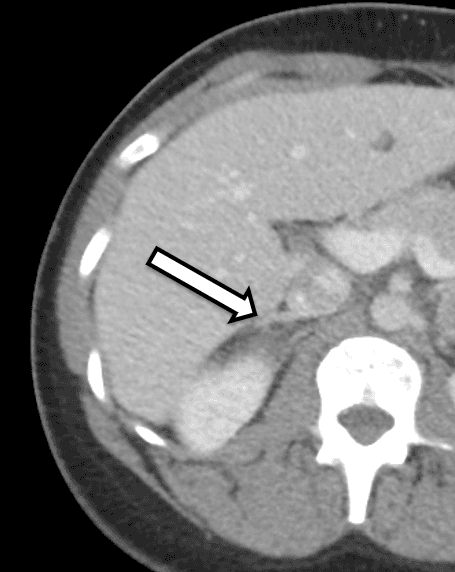

Bei der Patientin handelt es sich um eine 31-jährige Frau, die biochemisch eindeutige bilaterale Phäochromozytome aufwies. Sie hatte Symptome von Bluthochdruck und Herzklopfen, was zu weiteren Untersuchungen durch ihren Hausarzt führte. Ihre Laboruntersuchung war signifikant für erhöhte Metanephrine im freien Plasma bei 642 pg/ml (Referenzbereich < 57 pg/ml) und Normetanephrin bei 2284 pg/ml (Referenz < 148 pg/ml) sowie für erhöhte Metanephrine im Urin, was mit einem Phäochromozytom übereinstimmt. Die Schnittbildgebung umfasste eine CT des Abdomens mit IV-Kontrastmittel. Die CT zeigte bilaterale Nebennierenknoten mit Präkontrast-Hounsfield-Einheiten und allgemeine bildgebende Merkmale des bilateralen Phäochromozytoms (Abbildung 1). Eine genaue Überprüfung ihrer Bildgebung zeigte normal erscheinendes Nebennierenrindengewebe auf der rechten Seite (Abbildung 2), das für eine kortikalschonende Adrenalektomie auf dieser Seite förderlich wäre.

Wir bevorzugen es, dass sich der Patient innerhalb von ca. 3-6 Monaten nach der Operation entweder einer Nebennieren-CT oder einer MRT für die Operationsplanung unterzieht. In diesem Fall wurde der Patient an uns überwiesen, nachdem er ein CT hatte, das beidseitige Nebennierenmassen mit bildgebenden Merkmalen zeigte, die für ein Phäochromozytom verdächtig waren. In einer detaillierten Übersichtsarbeit bzw. ihrer Bildgebung zeigte sich, dass die untere mediale Extremität der rechten Nebenniere nicht betroffenes Nebennierenrindengewebe aufwies, das möglicherweise während der Resektion erhalten bleiben könnte.